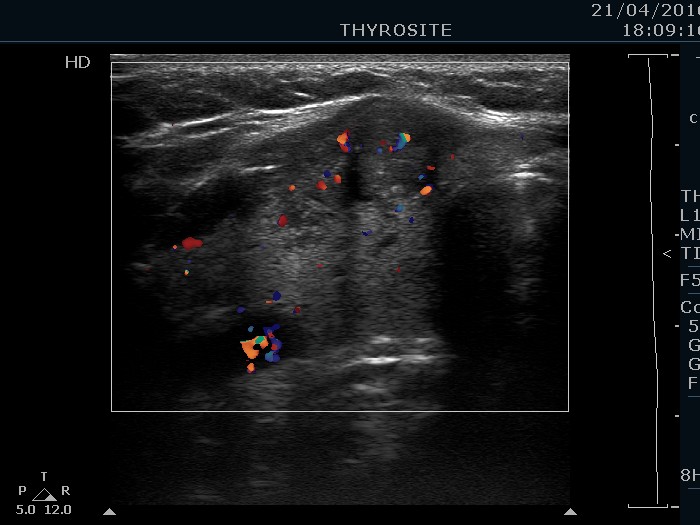

Right lobe, longitudinal scan

Right lobe, transverse scan, color Doppler mode. The nodule has intranodular vascularization.